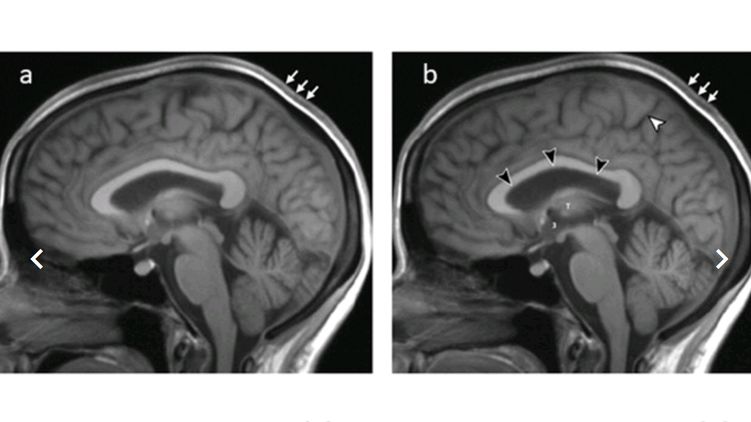

Всем 11 участникам исследования провели МРТ-сканирование мозга до начала полета, на следующий день после возвращения, а также через месяц, три месяца, полгода и год.

После полета у астронавтов наблюдалось увеличение объема головного мозга и циркулирующей в нем жидкости в среднем на 33 миллилитра (это 2%). Изменения сохранились и через год после окончания полета: объемы были увеличены на 28 миллилитров. Кроме того, у шести астронавтов наблюдалась небольшая деформация гипофиза - ключевого для эндокринной системы участка мозга. Его размер в среднем уменьшился с 5,9 до 5,3 миллиметров у 6 из 11 астронавтов.

Увеличение объемов головного мозга и циркулирующей в нем спинномозговой жидкости вызвано повышением внутричерепного давления из-за длительного пребывания в условиях микрогравитации.